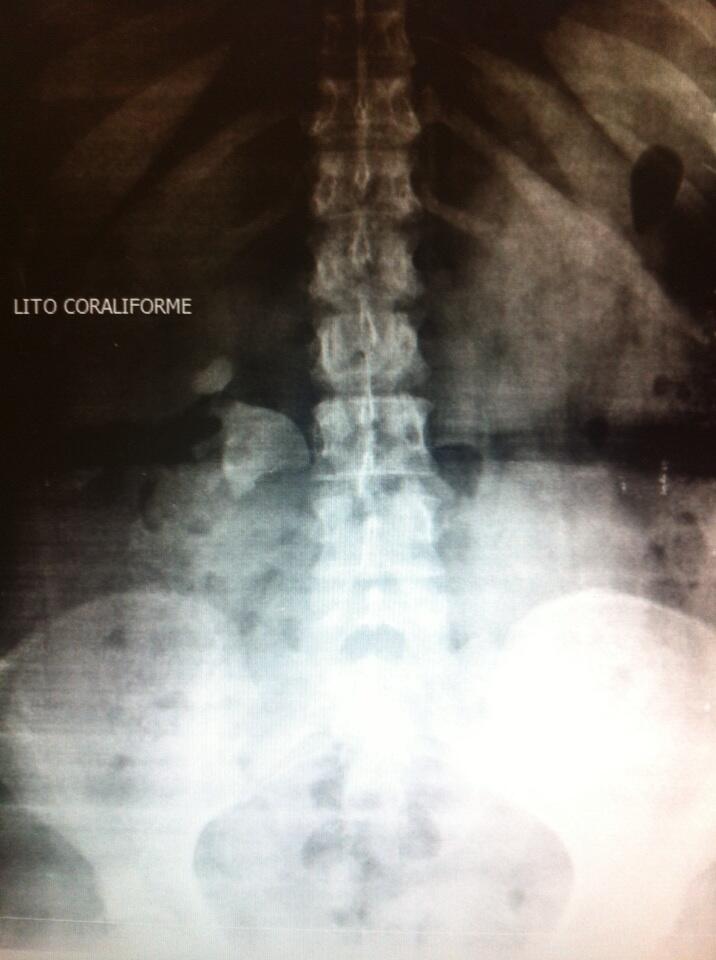

Corresponden al 10-15% de las litiasis siendo su prevalencia mayor en las mujeres que en los varones. Adoptan un color apagado o marrón claro, son infecciosas y a veces son tan grandes que forman los cálculos coraliformes que son unas grandes piedras que se forman dentro de las cavidades renales. Si no son tratadas a tiempo pueden producir pielonefritis (infección del riñón) y un importante deterioro de la función renal. El problema es que muchas veces estas piedras no dan síntomas en sus fases iniciales y se acaban descubriendo cuando tienen un tamaño considerable, muchas veces en el contexto de un estudio por infecciones urinarias de repetición.